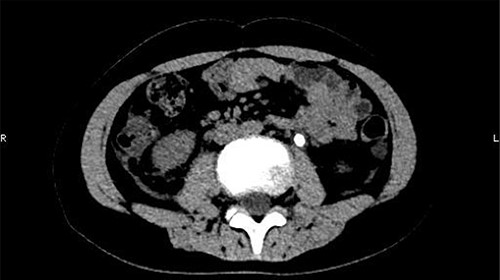

The patient was confined to bed, fasted and prescribed a daily intravenous infusion of cefazolin sodium pentahydrate, 2.0 g for 10 days. CT showed some irregular high-density shadows were present in the left renal pelvis (Fig. 1), and a small strip of high-density shadow was apparent in the bladder cavity (Fig. 2). Blood tests showed no abnormality in serum calcium concentration. Cefazolin sodium pentahydrate was discontinued immediately.

Some irregular high-density shadows was present in the left renal pelvis.